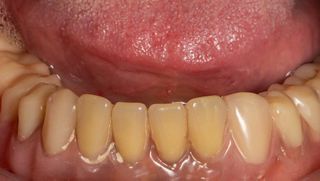

2c. Situation in the mandible: thin alveolar crest and residual teeth 33 and 43.

2c